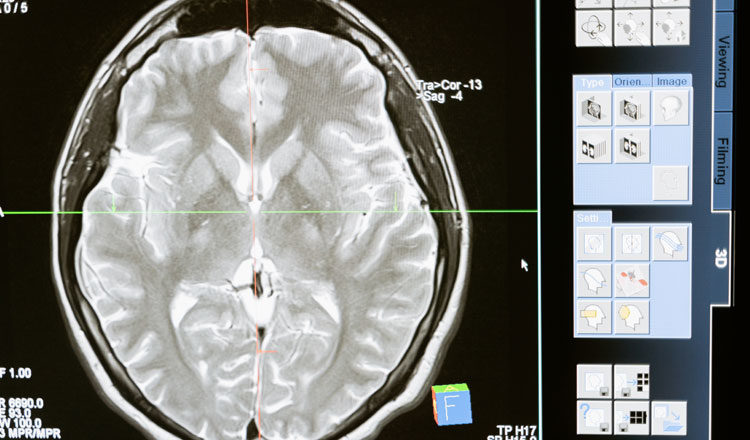

Επιστήμονες στο Νότιγχαμ ανακάλυψαν έναν νέο τρόπο χρήσης νανοσωματιδίων για την πρόκληση κυτταρικού θανάτου, γνωστού επιστημονικά ως “απόπτωση”, σε κύτταρα γλοιοβλαστώματος – μια από τις πιο επιθετικές μορφές καρκίνου του εγκεφάλου. Τα σωματίδια μπόρεσαν να στοχεύσουν ειδικά τα κύτταρα του γλοιοβλαστώματος, αφήνοντας αλώβητα τα υγιή κύτταρα.

Οι ερευνητές πιστεύουν ότι πρόκειται για την πρώτη “κβαντική θεραπεία”, αξιοποιώντας τις δυνατότητες της κβαντομηχανικής για την αντιμετώπιση του καρκίνου. Πιστεύουν ότι τα ευρήματά τους θα παράσχουν μια νέα και αποτελεσματική θεραπεία για τους όγκους του εγκεφάλου.